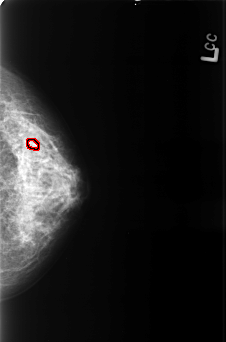

B_3426_1.LEFT_CC

LEFT_CC LINES 4440 PIXELS_PER_LINE 2936 BITS_PER_PIXEL 12 RESOLUTION 50 OVERLAY

FILE: B_3426_1.LEFT_CC.OVERLAY

TOTAL_ABNORMALITIES 1

ABNORMALITY 1

LESION_TYPE CALCIFICATION TYPE PUNCTATE-AMORPHOUS DISTRIBUTION CLUSTERED

ASSESSMENT 4

SUBTLETY 3

PATHOLOGY BENIGN

TOTAL_OUTLINES 1

BOUNDARY